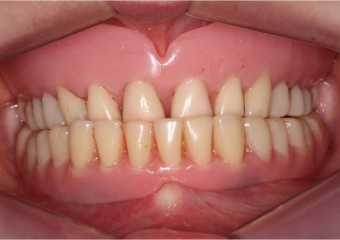

Imagem inicial - Clínica Cliniface

Imagem inicial